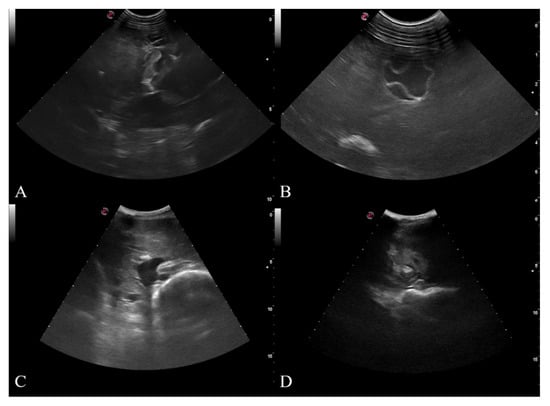

2.2. Ultrasound Examination and Fast Scanning Technique

- CL: unilocular anechoic cystic lesion with uniform anechoic content. The cyst wall is not visible.

- CE1: uniformly anechoic cyst with uniform anechoic content or fine internal echoes.

- CE2: cyst with internal septation, sometimes with a honeycomb appearance

- CE3: unilocular cyst that can show the presence of a daughter cyst.

- CE4: hypoechoic and hyperechoic matrix, the appearance resembles a ball of wool.

- CE5: cyst with partially or completely calcified wall.